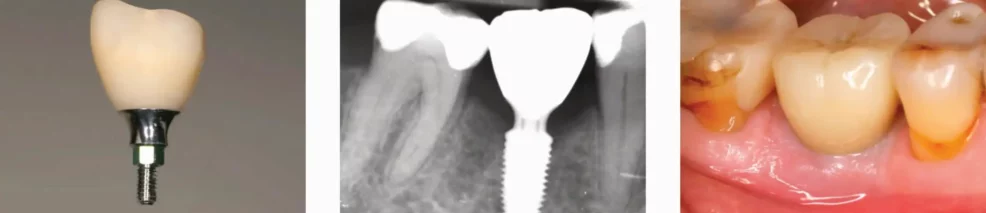

6 mm breed en 4,5 mm hoog healing abutment.

Goed initieel emergency profile.

Scanabutment correct geplaatst. Platte kant naar de buccaal gericht.

2,8 mm hoog en 5,7 mm brede Ti-base. Schoon en gedesinfecteerd.

Röntgenfoto na plaatsing.

Volledig Zirkonium kroon, biocompatibel en goede mondhygiëne mogelijk.